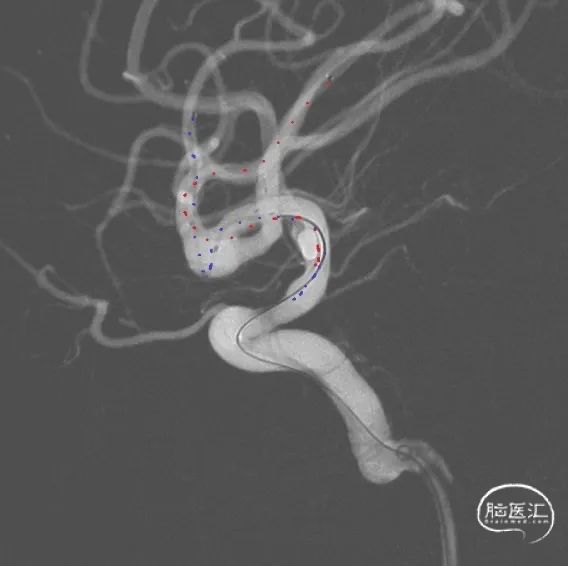

工作位术前造影及路图。

Synchro10微导丝引导两条SL-10微导管分别超选入右侧大脑中动脉下干(红管)和上干(蓝管)。

将3mm*21mm Atlas支架通过上干微导管输送到位,对位准确后,通过微导管成功释放。

释放完第一枚支架的SL-10微导管(蓝管)留在M1水平段不撤出,然后用微导丝将其引导穿过第一枚Atlas支架的网眼超选入MCA下干的另一分支,微导丝及微导管穿网眼过程中Atlas支架稳定。成功穿网眼建立第二枚支架通路后,将备用的SL-10微导管(红管)轻轻后撤,管头正好从下干落入动脉瘤腔内,留待填塞弹簧圈用。

经下干的SL-10微导管释放第二枚Atlas支架,形成“Y”型支架形态,充分保护上下两干,Atlas支架打开顺畅,影像下可清晰看到两端标记点完全打开。第二枚支架释放完毕后,顺势将该SL-10微导管经支架网眼顺利超选入瘤腔,拟双微管填塞。经一根SL-10微导管释放第一枚Target XL 4mm*12cm弹簧圈进行成篮。